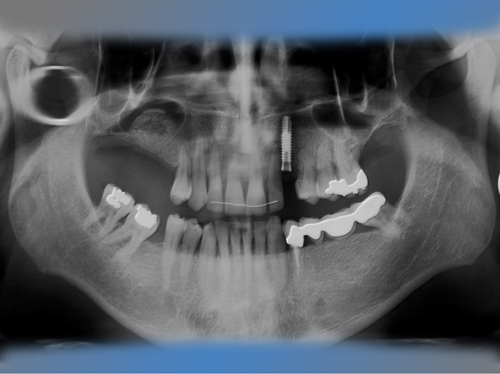

Félix Miquel Sempere acude en 2001 a la clínica dental IDIM tras varios intentos fallidos de colocación de implantes dentales en otra clínica dental.

En el maxilar superior tenía poco hueso debido a la presencia del seno maxilar, por lo que se le trato con la técnica de injerto óseo conocida como elevación de seno directa para poder colocarle implantes.

También se le sustituya el puente de la mandíbula que presentaba movilidad debido a caries en los dientes pilares por dos implantes y se le coloca otro implante en un canino superior ausente.